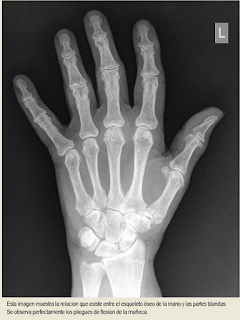

Como observamos en estas imágenes en las que se aprecia tanto el esqueleto como las partes blandas, la palma de la mano comprende huesos del carpo, los cinco metacarpianos y parte de las falanges de los dedos a excepción del pulgar.

Al igual que observamos que la muñeca comprende los huesos del carpo, su articulación con los metacarpianos de un extremo y su articulación con el radio del otro extremo.

Así que si nos referimos a la palma en un debate sobre crucifixión queremos referirnos a la plena palma ó al medio de la palma, que es el territorio de los metacarpianos, y si nos referimos a muñeca lo estamos haciendo al territorio de los huesos carpianos y sus articulaciones.

El debate debiera ser pues “clavo atravesando los huesos metacarpianos vs. clavo atravesando los huesos carpianos”.